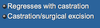

True/False: Prognosis for Dogs with Metastatic Mammary Tumors is Poor

True

*With Metastasis- Mean Survival Time is 5 Months